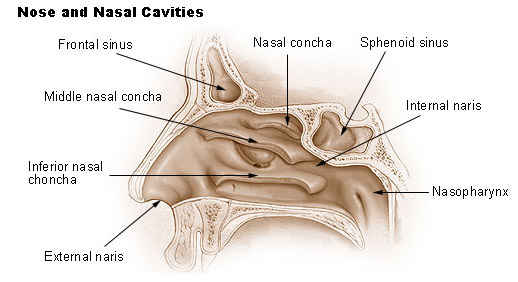

Just beneath each concha is a passage known as the meatus named for the adjacent turbinate.

The lateral nasal wall consists of inferior and middle turbinates and occasionally a superior or supreme turbinate bone. The turbinates consist of three ridges of thin shell like bone known as the nasal conchae. The nasal passages are lined with a membrane composed primarily of one layer of flat closely packed cells called epithelial cells.

Superior middle and inferior meatus. The nasal cavity extends from the external opening the nostrils. The nasal cavity is surrounded by a.

In bones behind your nose are your sphenoid sinuses. Anatomy of the nasal cavity. This region is divided into a labyrinth of slit like passages by multiple bony proturbances that fill the nose and act as shelves.

The exhaled air travels in the reverse path and leaves the body through the nasal cavity. The superior the middle and the inferior turbinates. Theyre lined with soft pink tissue called mucosa.

Role as a passage for inhaled air. Normally the sinuses are empty except for a thin layer of mucus. The ridges are named for their position.

During inhalation air enters through the nostrils and passes via the nasal cavity into the pharynx and larynx the next sections in the respiratory tract to eventually reach the lungs. Anatomy and physiology of the nasal cavity inner nose and mucosa introduction. Anatomy of the nose.

The external nose consists of paired nasal bones and upper and lower lateral cartilages. The nasal cavity refers to the interior of the nose. The nasal cavity is the most superior part of the respiratory tract.